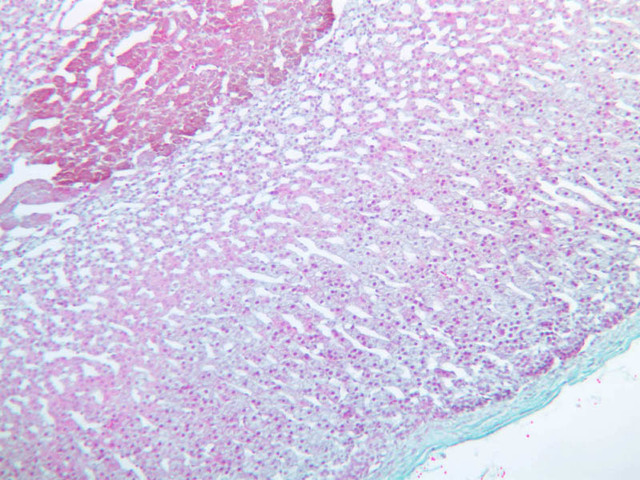

Examine slide B-56 (H&E [2.5x, 10x, 20x, 40x-labeled] [10x, 20x, 40x-labeled] [20x, 40x] [10x, 20x, 40x-labeled] [10x, 20x, 40x]). The connective tissue capsule of each parathyroid gland is continuous with that of the thyroid gland. It extends into the substance of the gland, dividing it into poorly defined lobules. Fat cells may separate the groups of cells and increase with age. Note the rich capillary network. The parenchyma is composed of two types of cells: (1) Principal or chief cells and (2) oxyphil cells. The polygonal chief cell is by far the more numerous cell type. Its nucleus is centrally located and has a vesicular chromatin pattern with a prominent nucleolus and its cytoplasm stains rather lightly. Oxyphil cells, which are less regular in shape and considerably larger than chief cells, are scattered singly or in small clusters. Their nuclei are smaller and more condensed than those of the chief cells and, owing to a very rich complement of mitochondria, their cytoplasm is distinctly acidophilic.

B56, Parathyroid, 2.5x (H&E) B56, Parathyroid, 10x (H&E) B56, Parathyroid, 20x (H&E) B56, Parathyroid, 40x Labeled (H&E) B56, Parathyroid, 10x (H&E) B56, Parathyroid, 20x (H&E) B56, Parathyroid, 40x Labeled (H&E) B56, Parathyroid, 20x (H&E) B56, Parathyroid, 40x (H&E) B56, Parathyroid, 10x (H&E) B56, Parathyroid, 20x (H&E) B56, Parathyroid, 40x Labeled (H&E) B56, Parathyroid, 10x (H&E) B56, Parathyroid, 20x (H&E) B56, Parathyroid, 40x (H&E)